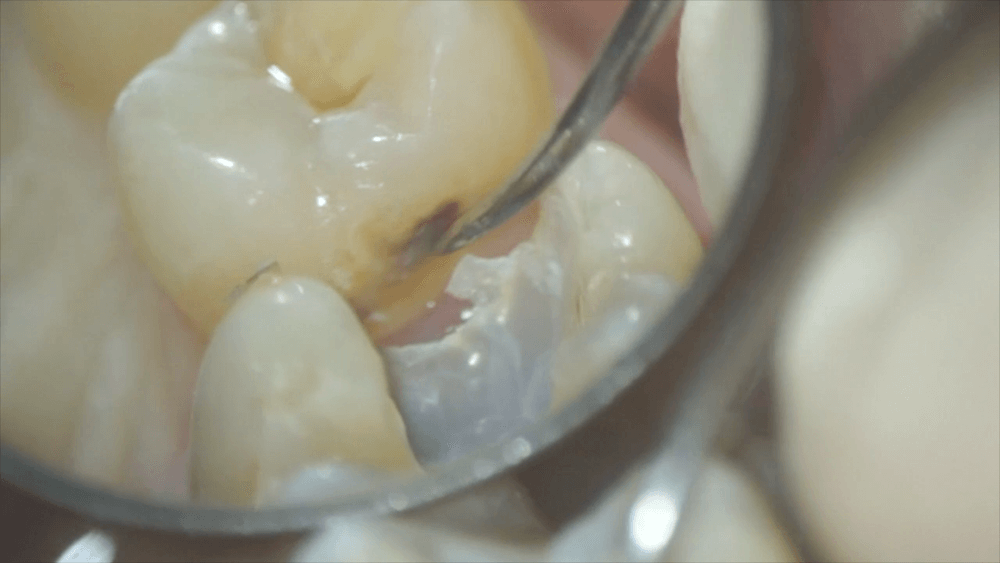

このつめ物をマイクロスコープを用いて除去します。

取り除くと、となりの歯の側面が見えました。黒くなっています。これは虫歯になりかかっている状態です。

この部分を触ると、虫歯の原因であるプラークがたくさん出てきました。